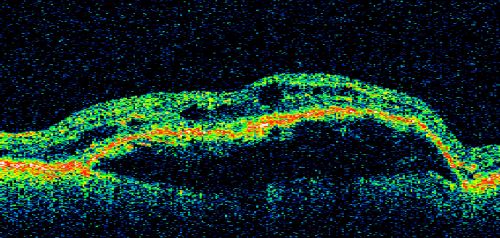

Pigment Epithelial Detachment with Subretinal Fluid and Exudate 20/400 Vision

87-year-old woman has wet age-related macular degeneration in the left eye.  She had treatment up north but there has been a gap in therapy and the vision in the left eye is poor.  Vision OD is 20/25, OS is 20/400